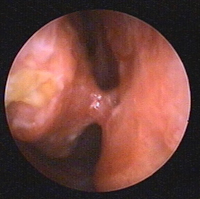

- efetuar um exame clínico da pirâmide nasal e do interior do nariz com um nasofibroscópio, nomeadamente se existir um problema respiratório associado

aspeto endoscópico das fossas nasais direita e esquerda exame clínico

exame endonasal

Ajuda a avaliar a obstrução nasal.

Avaliar a realidade da obstrução.

Procurar o local responsável (septo, cornetos inferiores, concha bolhosa).

Correção compatível com o gesto piramidal.

Procurar por patologia infecciosa.

Procurar sequelas de operações anteriores (perfuração do septo, flange sinecial).

Perfuração de divisórias   Pólipo da cavidade nasal Sinéquia do bulbo do corneto inferior

Nasofibroscopia